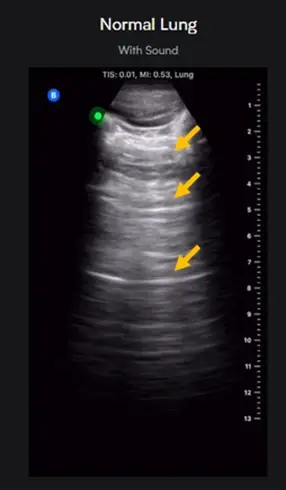

圖片為一張正常肺部 (Normal Lung) 的 B-mode 超音波影像。

- 胸膜線 (Pleural line):在影像上方,可見一條明亮且清晰的水平高回音線,這代表著壁層與臟層胸膜的交界面。

- 黃色箭號所指特徵:在胸膜線的下方,黃色箭號指出了數條與胸膜線平行、水平且等距排列的明亮線條。

- 影像意義:這些特徵性的水平線條在肺部超音波中被命名為「A線 (A-lines)」。A線的間距與「探頭皮膚表面到胸膜線的距離」完全相等,是正常且充氣良好的肺部最典型的超音波表現。

圖中箭號所指的水平等距亮線為 A線 (A-lines)。正常肺部充滿空氣,超音波在接觸到胸膜與空氣的交界面時會產生強烈反射。這些反射的聲波在胸膜與超音波探頭之間發生多次來回反射,導致超音波儀器在胸膜下方深處,以等於「探頭至胸膜距離」的等倍數深度,重製出多條平行的假影像。這種因為聲波在兩個強反射面間來回震盪而產生的現象,在物理學上明確定義為殘響假影 (reverberation artifact)。在肺部超音波篩檢中,看到明顯的 A線,代表該區域的肺部通氣良好,沒有被液體填滿或發生肺實質化 (consolidation)。